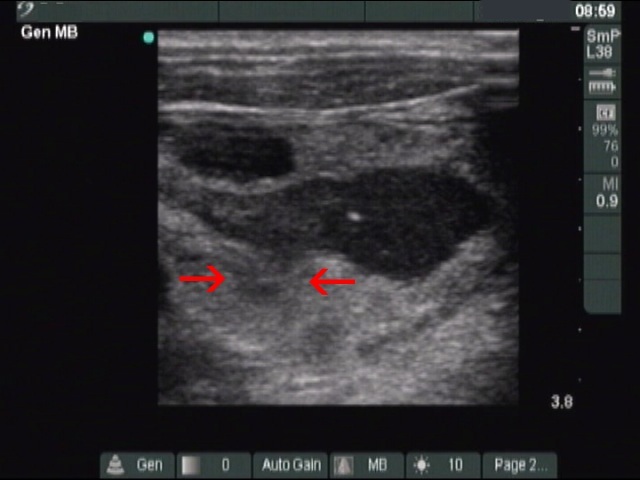

The composition of the nodule - case 353 (ultrasonographic picture 7b)

Right lobe, transverse scan. The tip of the needle can be seen within the cystic part of the nodule. The arrows point to a vessel which refilles the cyst while we were drawing off the lesion.